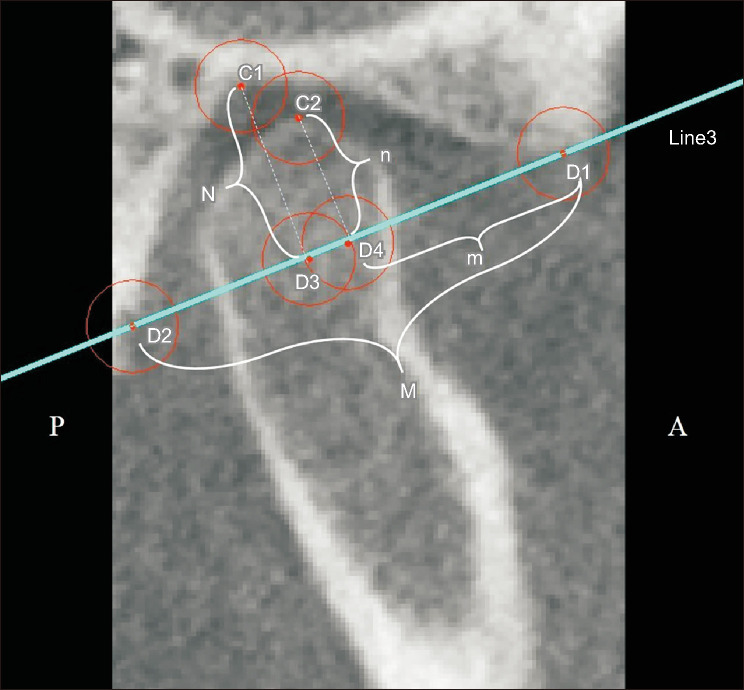

Methods: Overall, 88 mandibular condyles from 44 adult patients (20 female and 24 male) diagnosed with mandibular prognathism due to skeletal Class III malocclusion who underwent bilateral sagittal split ramus osteotomy (BSSRO) and Le Fort I performed using the manual condyle positioning method were included. Cone-beam computed tomography images obtained 1-2 weeks before (T0) and approximately 6 months after (T1) surgery were analyzed in three planes using 3D Slicer software. Statistical significance was set at P < 0.05 level.

Results: Significant inward rotation of the left mandibular condyle and significant outward rotation of the right mandibular condyle were observed in the axial and coronal planes (P < 0.05). The positions of the right and left condyles in the sagittal plane and the distance between the most medial points of the condyles in the coronal plane did not differ significantly (P > 0.05).